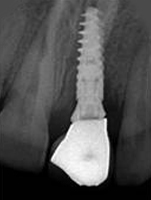

X-ray of Implant + Abutment

Single Tooth Implant

X-ray of Implant +

Abutment + Prosthesis

After Placement of Prosthesis